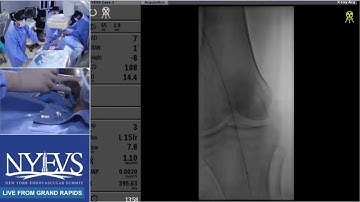

Live Case Presentation #1 Sessions In Clti Primary Pedal Access For Tibial Revascularization F Saab